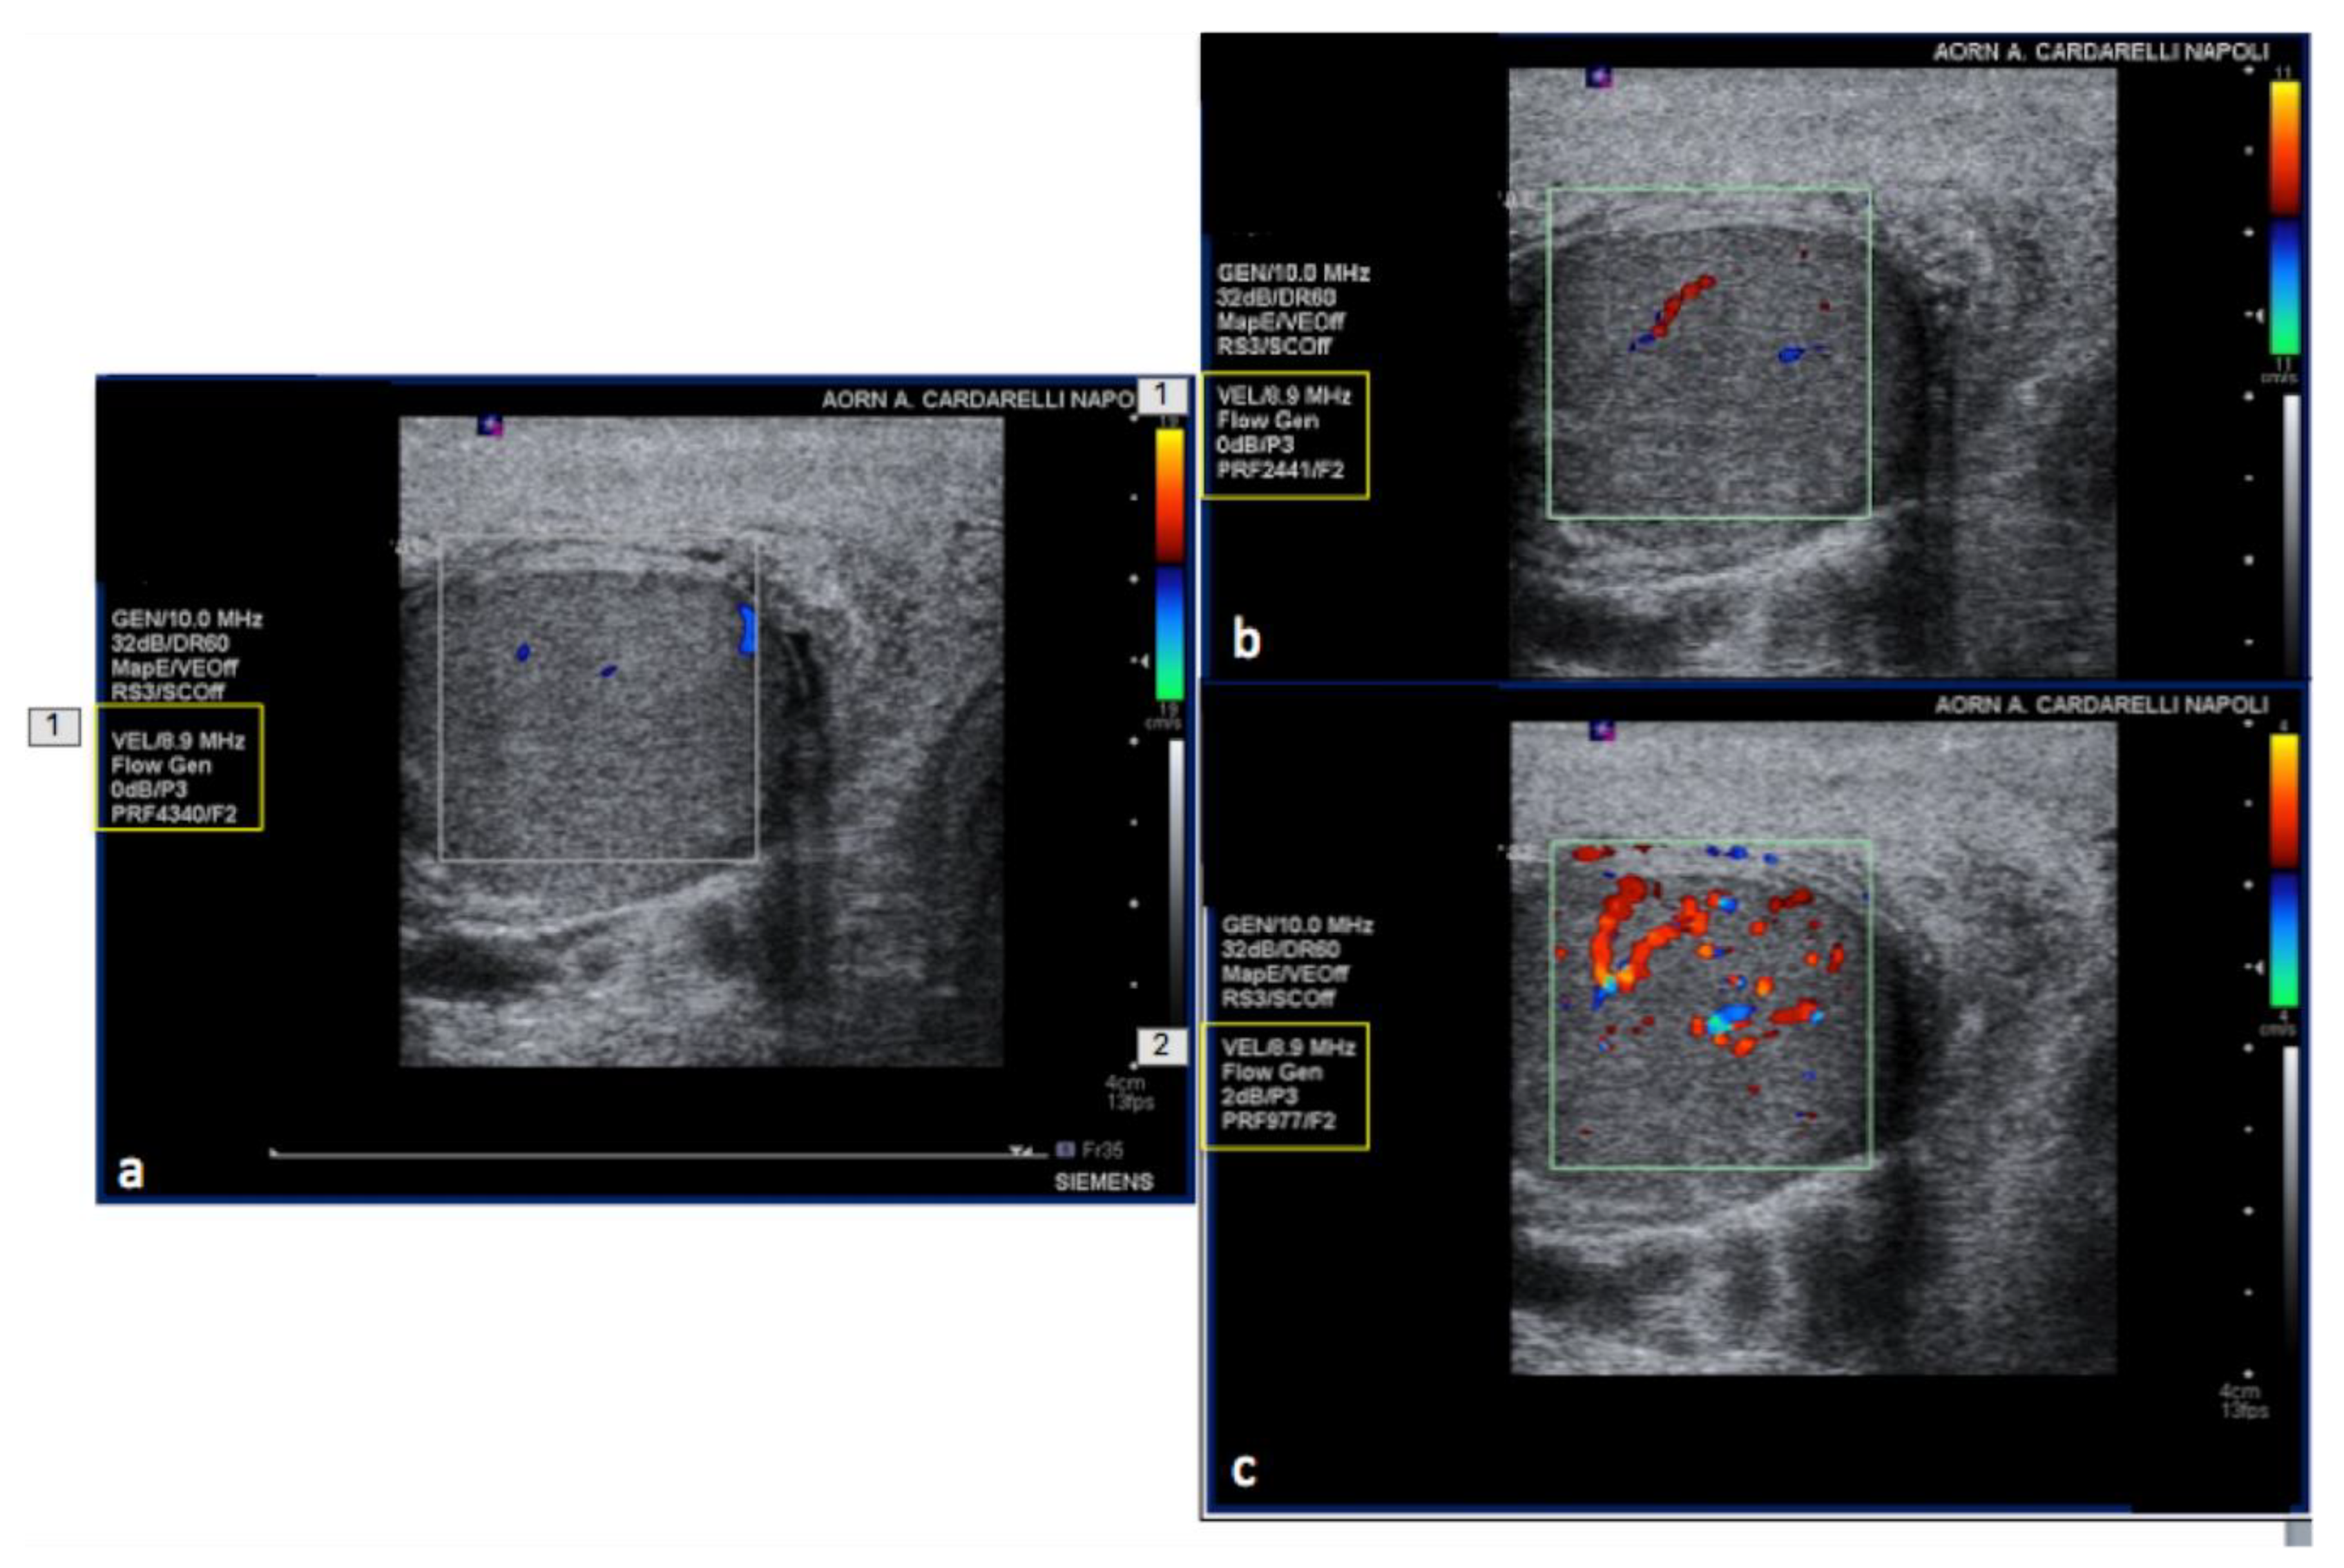

3.3. US-Setting Errors

| Steps | Color and Pulse Doppler Parameter | Remarks |

| 1st | Pulse repetition frequency (PRF) | Optimal PRF proportional to the flow to be studied and in principle must be lowered until it almost reaches the aliasing threshold. |

| 2nd | Size and position of the color box | The color box must be neither too wide, too small, too long nor too deep. |

| 3rd | Angle correction | To calibrate the velocity scale for the angle between the US beam and the blood flow being measured. Ideally, the direction of flow should be at an approximately 45–60° angle relative to the transducer. |

| 4th | Steering | Use probe positioning/beam steering to obtain satisfactory beam/vessel angle |

| 5th | Further settings | Wall filters; inversion of flow; color gain; spectral gain; baseline. |